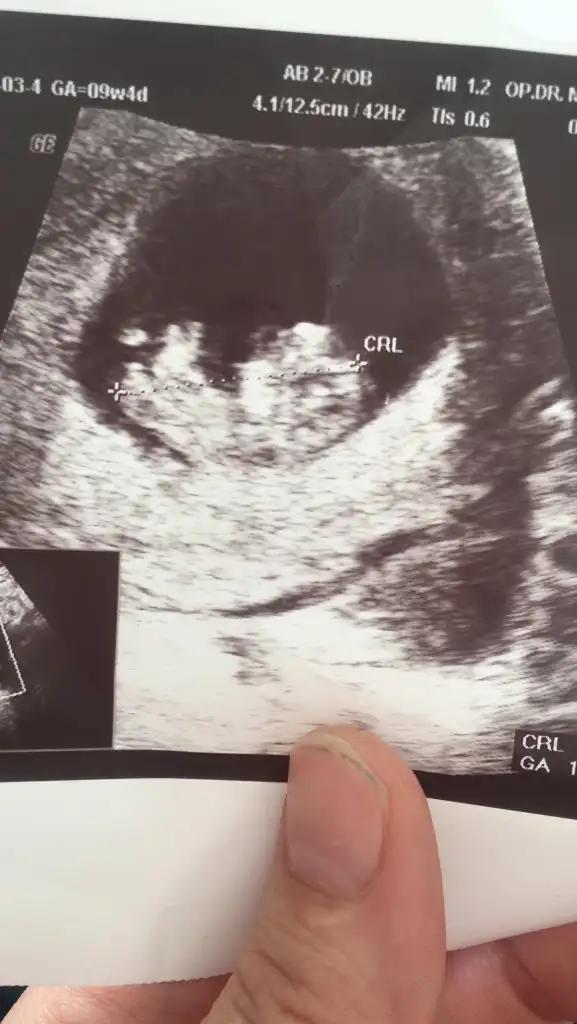

6+5 ve 7+6 acaba nedir çok merak ettim T Takitoki

Eklentiler

• IMG_20210216_173232.webp

32,7 KB · Görüntüleme: 116

• IMG_20210220_141159.webp

32,7 KB · Görüntüleme: 110

6+5 7+6 karından usg yazmayı unutmuşum tekrar attım T Takitoki